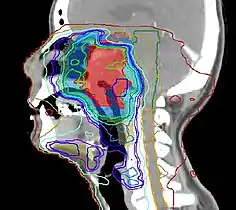

Nuclear Medicine is a fascinating application of nuclear physics. The first ten chapters of this wikibook are intended to support a basic introductory course in an early semester of an undergraduate program. Additional chapters cover more advanced topics in this field.

Radiation Oncology is a concise review of the radiation oncology field including a review of pertinent literature. Designed as a primer for students of radiation oncology, but may also be useful for those in practice to review areas of interest.